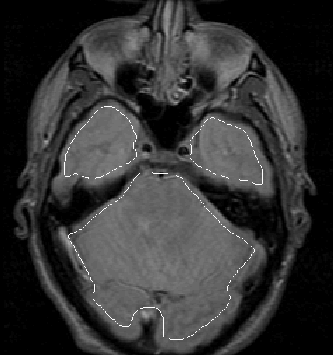

Figure 8.12: The initial brain mask for slice 7 of MRI Data Set 1 overlaid on the PD-weighted image.